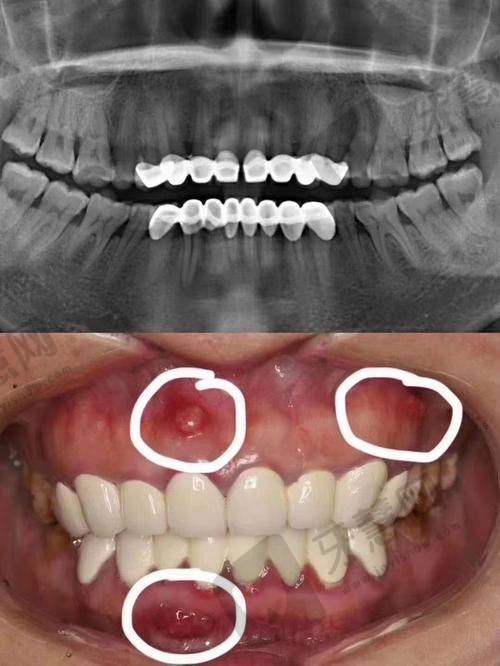

口腔综合治疗能力:口腔综合治疗科室可以处理常见的口腔疾病,如龋齿、牙周炎等,为患者提供全方面的口腔健康保护。